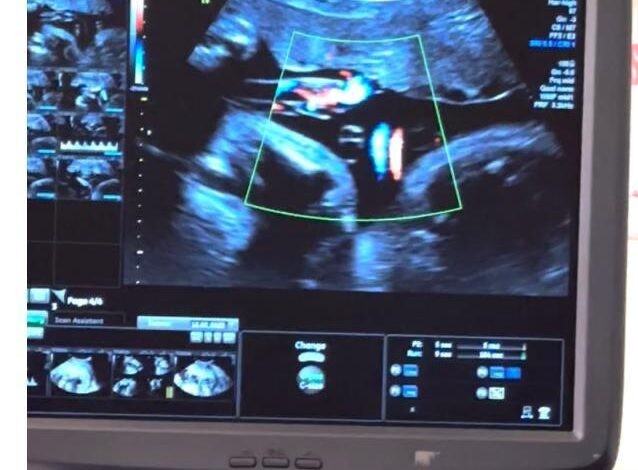

وتحدث د. ماجد فادن عن أنواع علاج الأجنة المتوفرة، مثل نقل الدم للأجنة المصابين بفقر الدم داخل الرحم، حيث يتم تشخيص فقر الدم للأجنة بالأشعة الصوتية الدقيقة وعمل بعض الفحوصات لدم الأم للأجسام المضادة التي تسبب تكسر في دم الجنين، مشيراً إلى أنه عندما يتم تشخيص الجنين بالخطورة العالية لفقر الدم الشديد يتم التدخل من قبل الفريق الطبي من خلال إبر متناهية الصغر للوصول إلى الدورة الدموية للجنين عن طريق الوريد للحبل السري واستعمال الأشعة الصوتية الدقيقة لإعطاء الجنين كميات من الدم المجهزة لمحاولة تجنب المضاعفات المترتبة على فقر الدم الجنيني الشديد والتي قد تؤدي إلى وفاة الأجنة لا سمح الله.

ومن طرق العلاج المقدمة رعاية حمل التوائم أحادي المشيمة (التوائم المتشابهة) والتشخيص المتقدم عن طريق الأشعة الصوتية لحالات متلازمة نقل الدم بينهم (Twin-Twin Transfusion Syndrome) والتي قد تؤدي إلى مضاعفات شديدة قد تصل إلى وفاة أحد الجنينين أو كلاهما في حال عدم التدخل السريع والمناسب، حيث يتم التدخل عن طريق استخدام منظار خاص متناهي الصغر يتم إدخاله عن طريق بطن الأم إلى داخل الرحم تحت التخدير الموضعي مما يمكن الفريق الطبي من فحص المشيمة والتعرف على الأوعية الدموية المسببة للمتلازمة ويتم كيها وإغلاقها باستخدام تقنية الليزر المخصص لمثل هذه الإجراءات والذي بدوره يحل المشكلة من جذورها. هذا التدخل يمثل أفضل تدخل لحل المشكلة وتحسين فرص النجاة للطفلين.